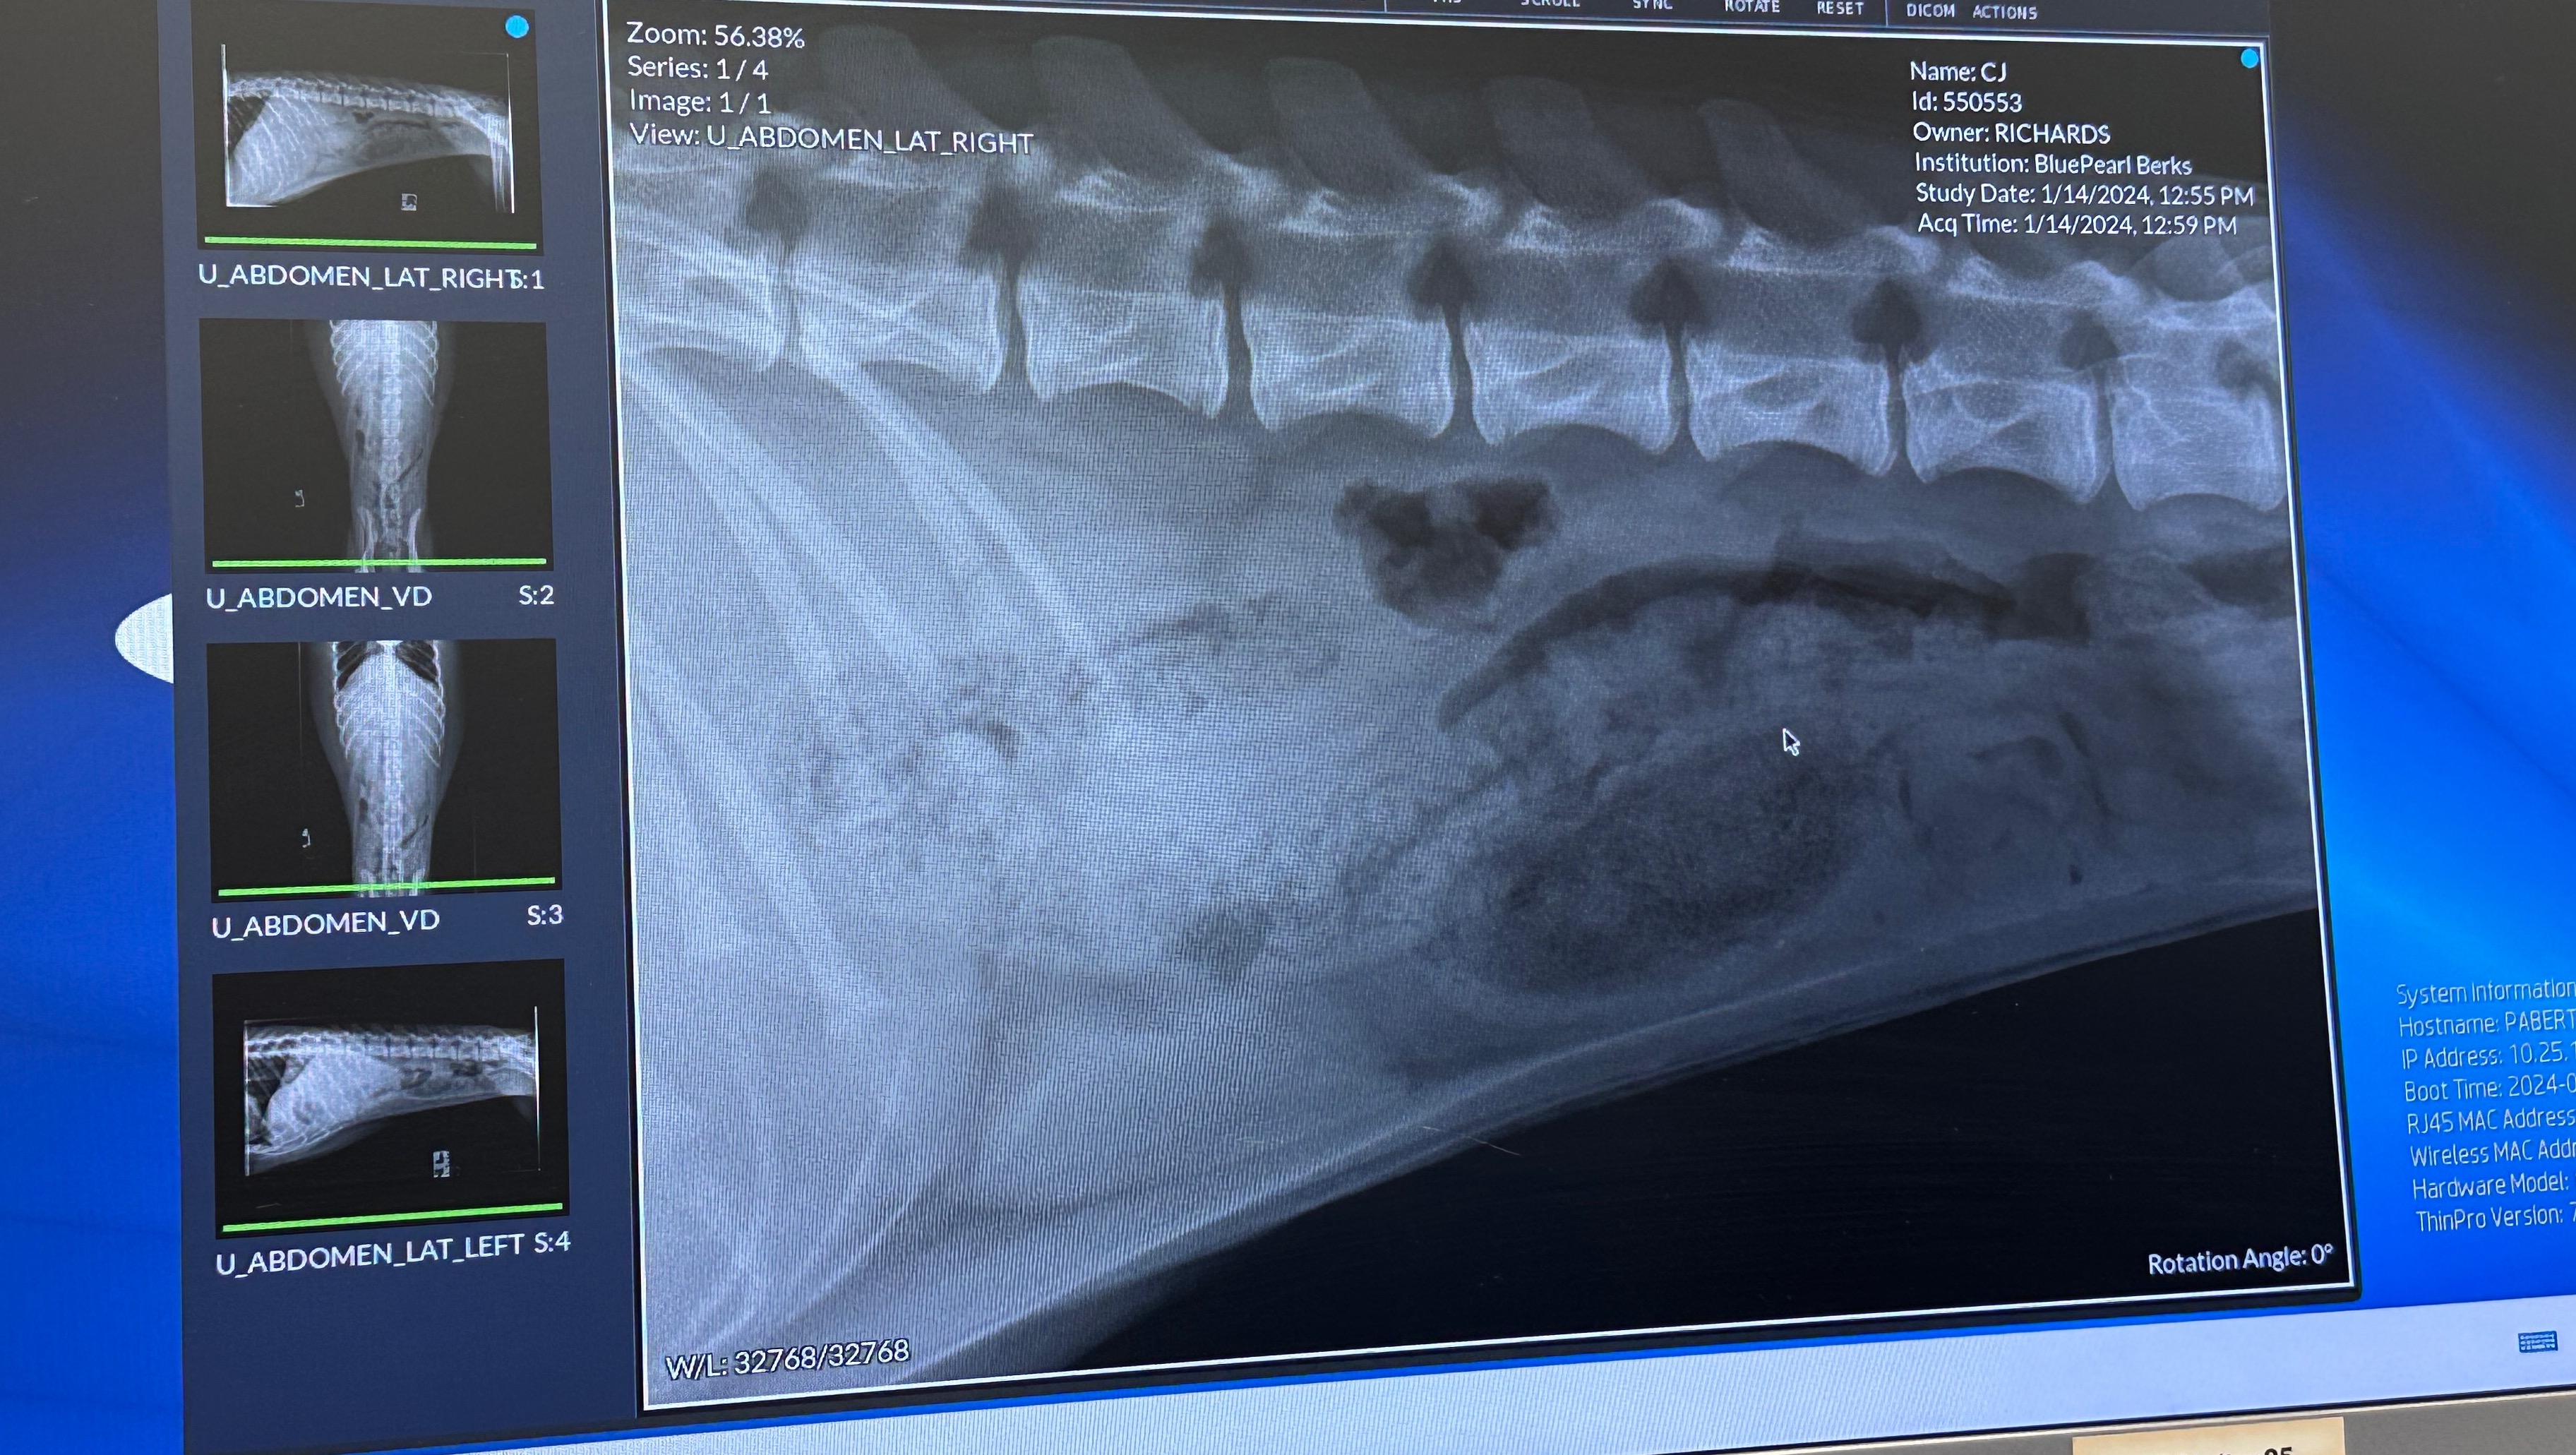

I took her to BluePearl Emergency Hospital in Shillington, PA, as it was the only emergency hospital open on a Sunday, and she was diagnosed with an intestinal foreign body, and it needs to be surgically removed because she won’t pass it on her own.

The estimate BluePearl gave me to do surgery tonight around, 01/14/2024, was between $7,000-$8,500, after doing initial work up on her which was $899.50. I am happy to send anyone who wants to see the records/invoice, copies. As well as any imaging.